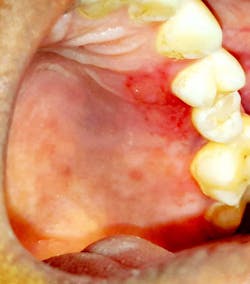

Case no. 2

The provisional diagnosis was COVID-19–related oral lesions. The case was managed with topical triamcinolone acetonide (Kenacort) 0.1% paste, doxycycline and benzalkonium chloride mouthrinses, and topical benzocaine 5% gel.

- Multiple palatal and oropharyngeal petechial lesions

- Palatal and oropharyngeal erosions and ulcerative lesions

- Severe pain over the lesion area

- Partial paresthesia surrounding the lesions

- Irregular areas of blanching involving the palate

- Burning sensation of palate and oropharynx, and dysphagia

- Palatal and oropharyngeal tenderness and soreness

- Necrotic pseudomembranes covering the erosive/ulcerative lesions